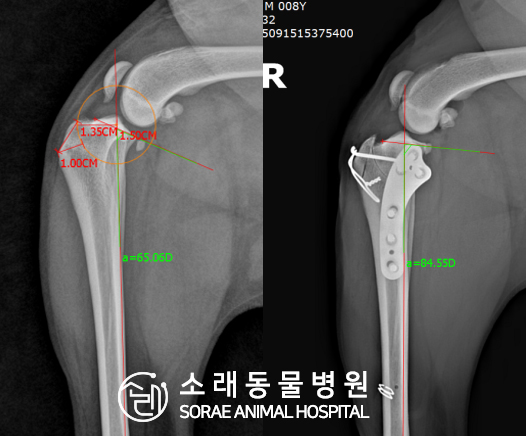

계산식으로 사전에 계획해두었던 플랜에 따라 경골을 절제하고

플레이트와 스크류를 사용하여 임플란트를 적용해 주었습니다.

반대 방향으로 밀려나 어긋나있던 대퇴골과 정강이가

제 자리를 찾으면서 무릎의 각도가 교정된 것을 확인할 수 있습니다